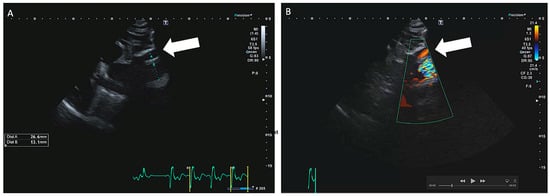

Bei einem 63-jährigen Patienten besteht ein Status nach mechanischem Aortenklappenersatz 1994 mittels St. Jude Medical© 25 mm bei kombiniertem Aortenklappenvitium, notfallmässigem Ersatz der Aorta ascendens mit 30-mm-Gefässprothese und Erhalt der Aortenklappenprothese im hypothermen Kreislaufstillstand bei Aortendissektion Typ A im Jahr 2001 und erneuter Reoperation bei Nahtaneurysmen mit Ersatz der Aorta ascendens und des Aortenbogens mit Haemoshield-Gefässprothese im Jahr 2003. Bei einer routinemässig durchgeführten Nachkontrolle durch den niedergelassenen Kardiologen wurde mittels transthorakaler Echokardiographie (TTE) ein perfundiertes Pseudoaneurysma im Bereich des proximalen Aortengrafts festgestellt (Abbildung 1). Daraufhin wurde der klinisch beschwerdefreie und hämodynamisch stabile Patient zur dringlichen Computertomographie (CT) in ein peripheres Spital überwiesen. Dort bestätigte sich der Verdacht eines Pseudoaneurysma im Sinne eines Nahthaneurysma (ca. 47 × 19 × 44 mm) ausgehend von der Aorta-ascendens-Prothese mit hochgradigem Verdacht auf Graftdehiszenz zwischen Ascendes- und Aortenbogengraft (Abbildung 2).

Abbildung 1. Nachweis des perfundierten Pseudoaneurysma (weisser Pfeil) in der echokardiographischen Kontrolle (A: parasternale lange Achse; B: mit Farbdoppler). Dabei zeigt sich die systolisch perfundierte Höhle vor dem Aortengraft.